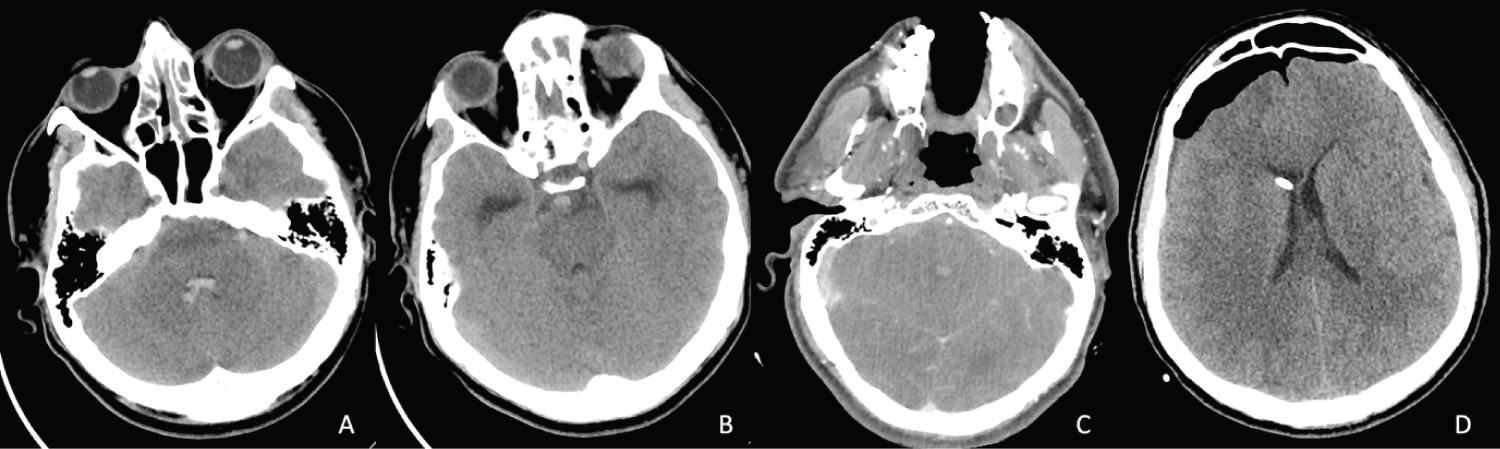

Figure 3: Head Computed tomography (CT) scans of case 3. (A,B) Initial Non-contasted CT scan demonstrating the acute subarachnoid hemorrhage anterior to the brainstem and inside the 4th ventricle; (C) CT angiography (CTA) that did not show any aneurysms or vascular malformations of the basilar artery and its branches; (D) postoperative CT scan showing the placement of the external ventricular catheter inside the right lateral ventricle, as well as a moderate amount of pneumocephalus after trephination. View Figure 3

This 38-year-old male diagnosed with COVID-19 three weeks prior to presentation had no previous medical history. Upon admission in another center, he complained of headache, nausea and vomiting, followed by a rapid decline in consciousness and increased agitation, then culminated by generalized seizures. He was transferred to our department after the initial CTA (Figure 3) showed a pretruncal nonaneurysmal subarachnoid hemorrhage that spread into the fourth ventricle and occipital horns of the lateral ventricles, causing obstructive hydrocephalus. No intracranial vascular lesions could be identified. Neurological examination revealed a GCS of 13 (M6, V4, O3), no discernible motor deficit, no lesions of the cranial nerves, the presence of increased intracranial pressure syndrome, and reactive pupils. Rapid COVID-19 antigen test performed just before transfer was positive. Prothrombin time and INR (international normalized ratio) were slightly increased, although not as much as to preclude surgery. Therefore, we initiated the surgical COVID-19 circuit and performed the insertion of an EVD on the right side. CSF was tinted red by fresh blood and under significant pressure.

Postoperatively, his evolution was mildly favorable, with the amelioration of the neurological status (GCS of 15 on postoperative day 2) and headache. Control CT scan disclosed the correct placement of the EVD, shrinkage of the ventricles, mild diffuse cerebral edema and no signs of an additional hemorrhage. He presented an episode of marked difficulty while breathing on postoperative day 3, for which the anesthesiology team decided to intubate. The pulmonary CT scan was evocative of COVID-19 (ground-glass opacities in both lungs), however PCR test returned negative. Furosemide, dexamethasone and mannitol therapy was initiated. Extubation occurred on the following day, the patient being aware, cooperative, and stable. However, after 5 days, the EVD began to show signs of blockage, the patient becoming somnolent. Control CT scan confirmed our suspicion by showing enlarged ventricles. As such, the EVD was replaced on day 6. Afterward, the patient regained awareness. Subsequent COVID-19 PCR tests all had negative results, the patient being transferred to our regular ICU compartment. CSF tests revealed an infection with Klebsiella specie, for which antibiotic lavage via the EVD was started. Tracheobronchial suction culture was positive for Acinetobacter baumannii. He currently remains in the ICU, with a decreased sense of awareness.